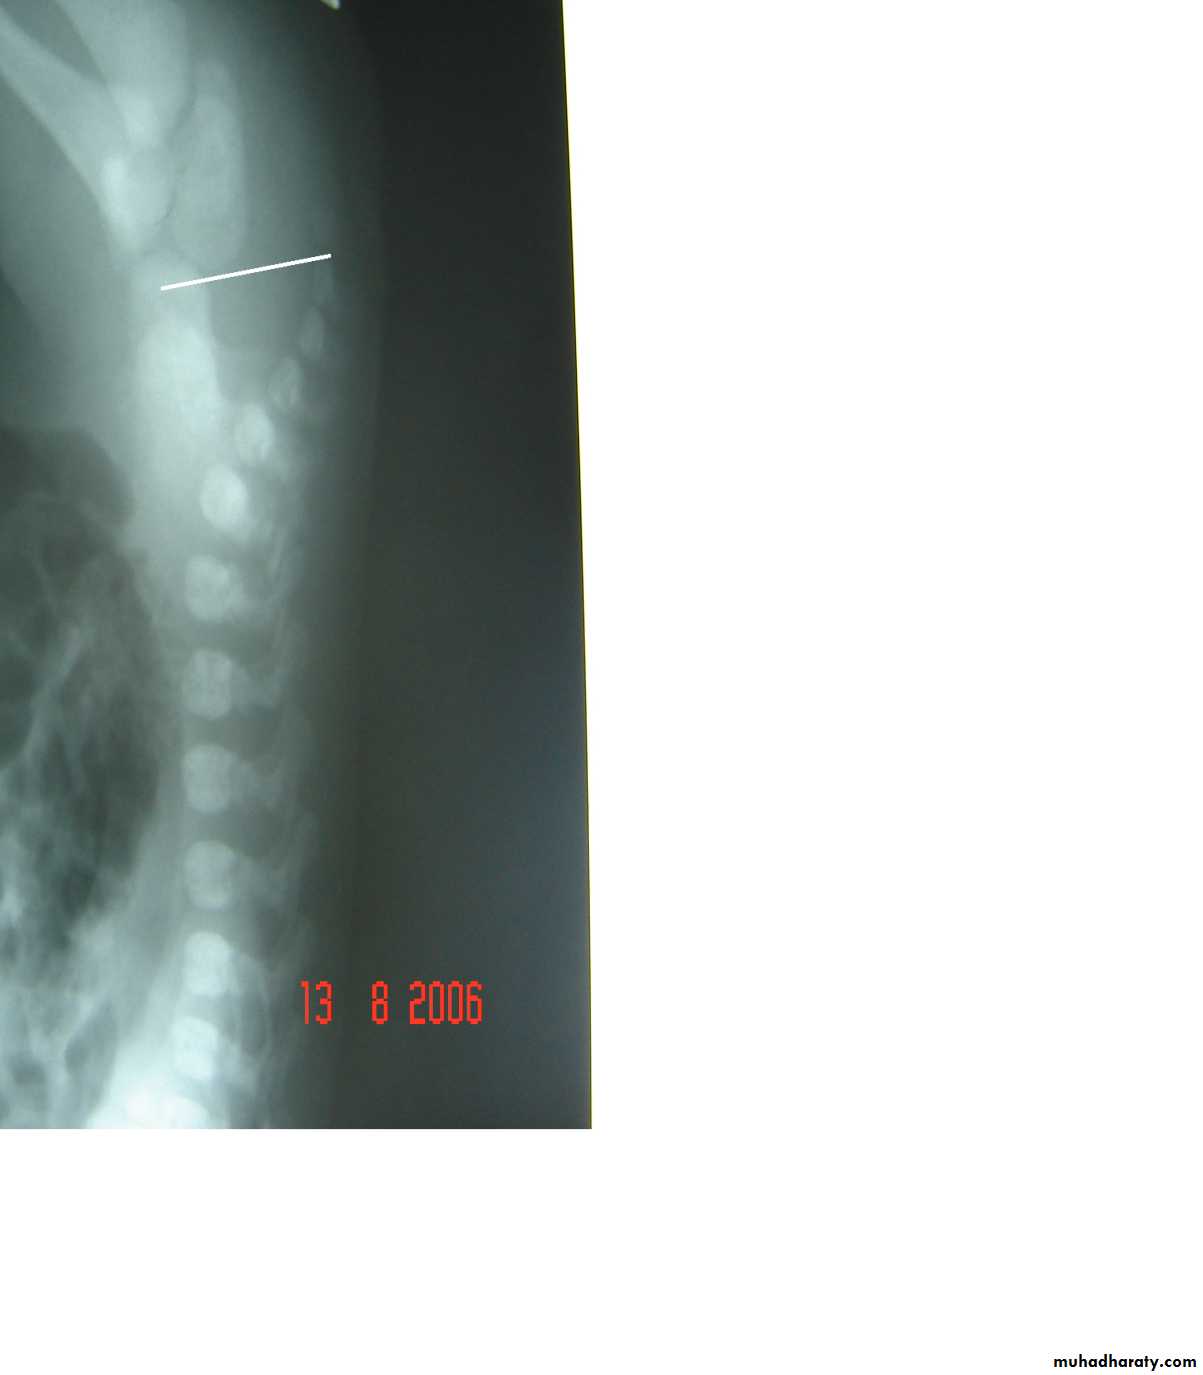

Diaphragmatic eventration

plication